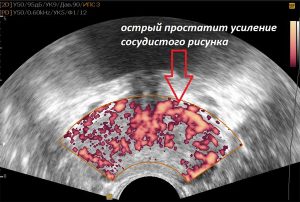

Prostat vəzinin adenomasının diaqnozun qoyulması kifayət qədər asandır. Artıq ilkin tanışlıq zamanı təcrübəli həkim müayinə olunan şəxsdə adenomanın olması barədə şübhələnə bilər. Sonra barmaqla rektal müayinə aparılır. Arxa (anal) dəlikdən düz bağırsağa daxil olmaqla həkim barmaqla prostat vəzini əlləyir, onun ölçülərini, hüdudlarını, konsistensiyasını müəyyən edir. Xəstəyə həmçinin USM, qan və sidiyin ümumi müayinəsi, qanın prostatspesifik antigenə (PSA) müayinəsi təyin edilir. PSA spesifik zülal olub, səviyyəsinin yüksəldiyi hallarda həkimlər xəstədə prostatit, prostat vəzinin adenoması, həmçinin prostat vəzinin xərçənginin olması barədə düşünə bilərlər. Qanda PSA-nin miqdarının təyin edilməsi çox vacib bir müayinə olub, yaşı 45-dən artıq olan bütün kişilərdə, ildə iki dəfə olmaqla, profilaktik müayinələr zamanı təyin edilməlidir.